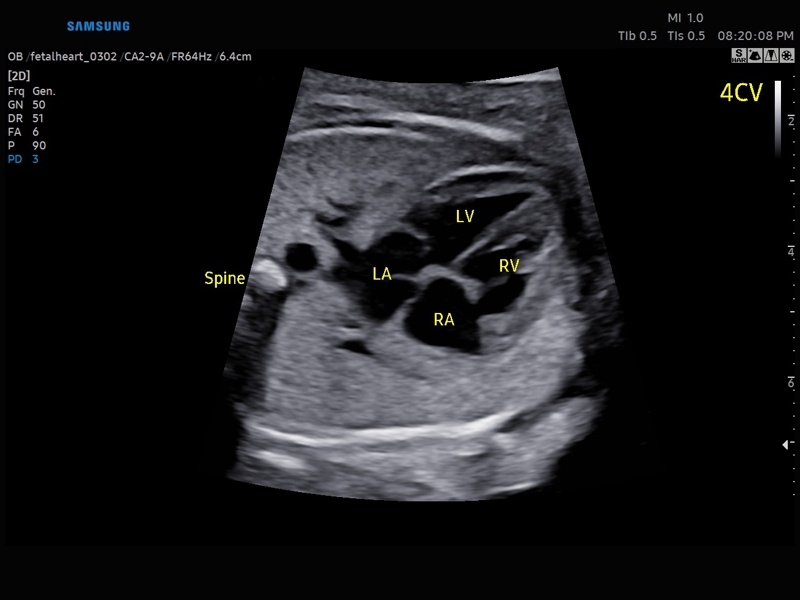

• Акушерство и гинекология

• Сердце плода:измерения в В-режиме (отношение площади сердца и грудной клетки), измерения в М-режиме (толщина межжелудочковой перегородки в диастолу, конечнодиастолический размер левого желудочка, толщина задней стенки левого желудочка в диастолу, толщина межжелудочковой перегородки в систолу, размер левого желудочка в систолу, толщина задней стенки левого желудочка в систолу, внутренний размер правого желудочка в диастолу), измерения в режиме спектрального допплера (легочный ствол, артериальный проток, нижняя полая вена, венозный проток, восходящая аорта, нисходящая аорта, трансмитральный кровоток, митральная регургитация, трикуспидальный кровоток, трикуспидальная регургитация, индекс преднагрузки, ЧСС).

• МодульSTIC- объемная динамическая визуализация сердца плода.